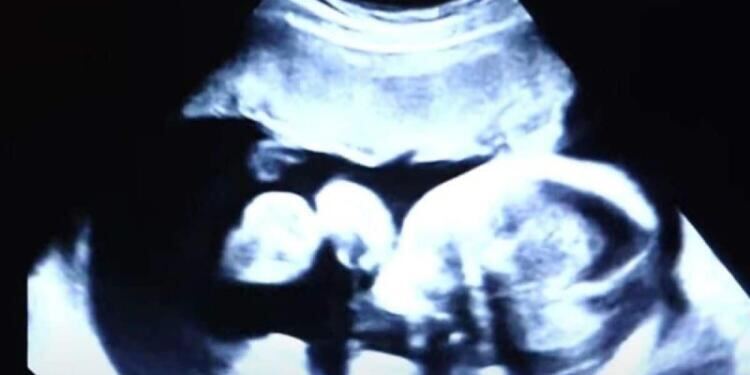

Μια 52χρονη προσφέρθηκε να γίνει παρένθετη μητέρα. Με την βοήθεια της εξωσωματικής γονιμοποίησης, έμεινε έγκυος όχι σε ένα, αλλά σε δύο μωρά!

Έκανε καθημερινά ενέσεις ορμονών και εβδομαδιαίους υπερήχους. Στα μισά της εγκυμοσύνης, η 52χρονη άρχισε να παρατηρεί αιμορραγίες. Φοβήθηκε ότι θα απέβαλε, αλλά οι γιατροί την διαβεβαίωσαν ότι όλα ήταν εντάξει.

Μετά από 37 εβδομάδες, ήρθε η ώρα να γεννηθούν τα μωρά, αλλά με κάποια μικρά απρόοπτα, όπως θα δείτε στο παρακάτω βίντεο.